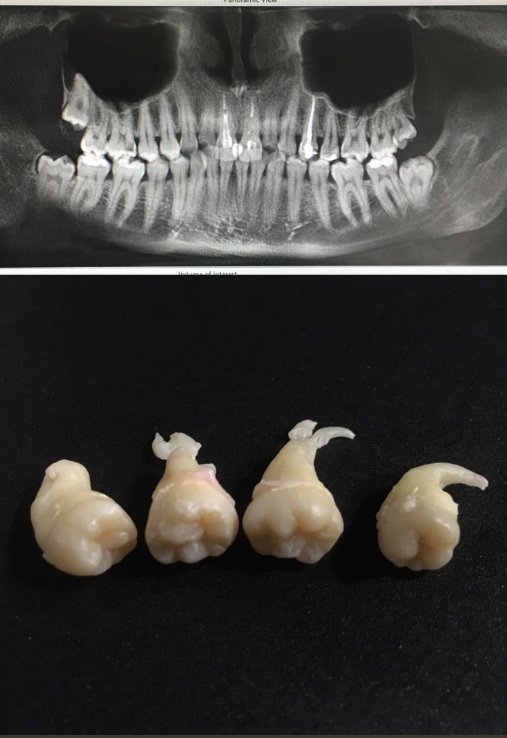

Сучасне обладнання забезпечує точність роботи та знижує ризик ускладнень, які можуть виникнути через дешеві послуги та недостатню кількість оснащення. В нашій клініці ми маємо можливість зробити як прицільні рентген-знімки, так і комп'ютерну томограму, що є дуже важливим етапом під час видаленні зубів мудрості.

— Видалення зубів мудрості без рентгену чи КТ – це значний ризик як для пацієнта, так і для лікаря. Ми не можемо працювати з тим, чого не бачимо, і відповідно – спланувати процедуру.

Зуби, які не прорізалися, часто розташовані близько до нижньощелепного нерва. Тож є ризик його травмування або пошкодження. А це може призвести до втрати чутливості частин обличчя та інших ускладнень.

Ми завжди використовуємо знімки для оцінки кожного випадки, ретельно плануємо свою роботу й лише після цього розпочинаємо видалення.

У нашій клініці є як комп’ютерний томограф, так і рентген, тож усе необхідне можна зробити на місці.